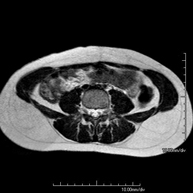

RM de Paret abdominalProva diagnòstica no invasiva que consisteix en l'obtenció d'imatges d'alta definició anatòmica de la paret abdominal mitjançant l'ús d'un camp electromagnètic i ones de ràdio (amb un emissor i un receptor). No utilitza radiació ionitzant. Està indicada en l'estudi de lesions de la paret abdominal i solen correspondre a bonys que detecta el pacient o a dolors en aquesta regió anatòmica. De vegades s'ha d'utilitzar contrast paragmanètic (Gadolini) per completar l'estudi.